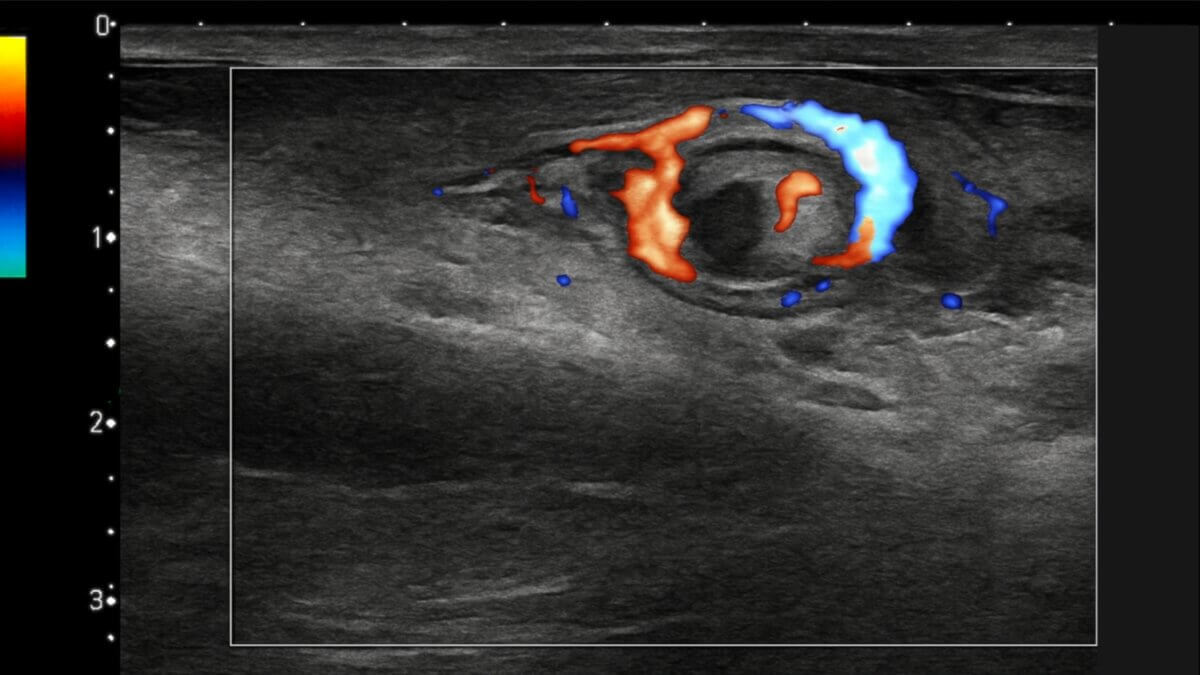

In der Sonographie zeigt sich eine spiralförmige Verdrehung des Samenstrangs, typischerweise im Bereich des äußeren Leistenrings oder Skrotalraums. Der Befund kann bei kompletter Torsion (≥ 360°) und auch bei inkompletter Torsion (< 360°) nachgewiesen werden.

Farbduplex-Sonographie

In der Farbduplex-Sonographie zeigt sich ein reduzierter oder aufgehobener Blutfluss im Hoden. Die Perfusion ist im Seitenvergleich asymmetrisch. Bei der Duplexuntersuchung des spiralförmig verdrehten Samenstrangs zeigt sich ein strudelförmiges Flussmuster.